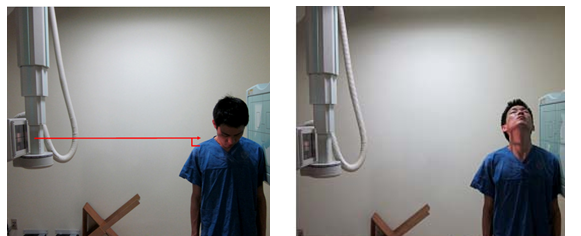

C-Spine Dynamogram

1. 목적

- C-spine의 정상적인 전후 운동과 각 spine간의 불안정성에 의한 추체의 미끄러짐, 추간강의 압축이나 벌어짐, dislocation 등의 병변 유무를 관찰한다.

2. 검사법

1) 환자자세

① FLEXTION은 C-SPINE LATERAL 자세에서 몸은 고정하고 고개만 숙이도록 한다.

② EXTENTION 몸은 고정하고 고개만 천장을 보도록 한다.

③ C4(adam’s apple)를 향해 수직 입사한다

2) 호흡법 : 움직임이 없도록 숨을 멈춘 후 검사한다.

5) 촬영 거리 : SID는 180cm으로 촬영한다.

6) 영상 결과